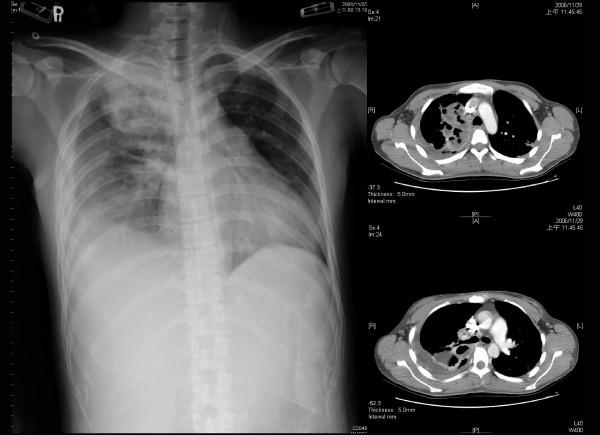

From January 2004 to December 2006, we retrospectively reviewed 259 patients diagnosed with pleural empyema who received thoracscopic decortications of the pleura in a single medical center. We evaluated their clinical data and analyzed their chest computed tomography scans. Outcomes of pleural empyema were compared between groups with and without lung abscess.

2004年1月至2006年12月,我们回顾性分析了在单一医疗中心接受胸腔镜胸膜剥脱术的259例诊断为脓胸的患者。我们评估了他们的临床资料并分析了胸部计算机断层扫描。比较有和没有肺脓肿的脓胸患者的预后。